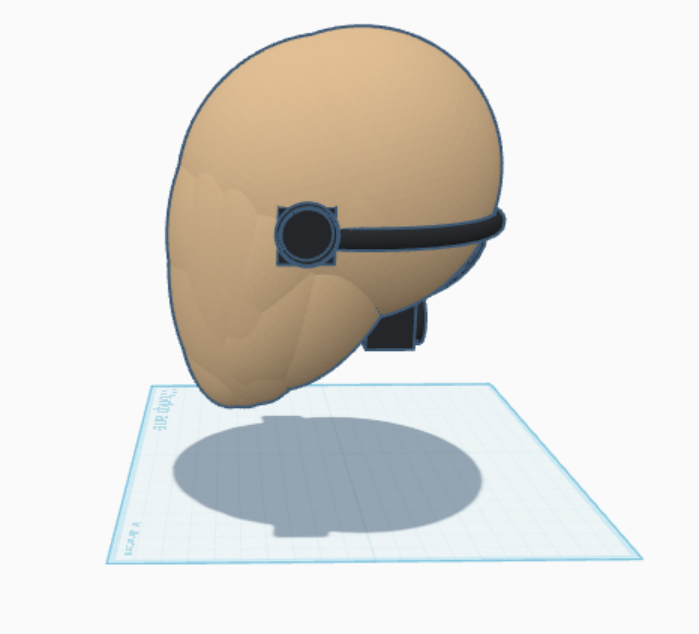

Build

Putting it all together, we created a high quality prototype of TONHI, proving that a design of this nature can be made in the future.

Transcranial Dopplers

Transcranial ultrasound dopplers will be placed at both transtemporal lobes and the suboccipital lobe of the patient to capture blood flow information and intracranial pressure.